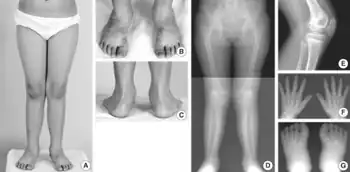

Autosomal recessive multiple epiphyseal dysplasia (ARMED), also called epiphyseal dysplasia, multiple, 4 (EDM4), multiple epiphyseal dysplasia with clubfoot or –with bilayered patellae,[1] is an autosomal recessive[2] congenital disorder affecting cartilage and bone development. The disorder has relatively mild signs and symptoms, including joint pain, scoliosis, and malformations of the hands, feet, and knees.[3]

Some affected individuals are born with an inward- and downward-turning foot (a clubfoot). An abnormality of the kneecap called a double-layered patella is also relatively common. Although some people with recessive multiple epiphyseal dysplasia have short stature as adults, most are of normal height. The incidence is unknown as many cases are not diagnosed due to mild symptoms.

The clinical presentation of this condition is consistent with:[4]

- Clubfoot

- Clinodactyly

- Skeletal dysplasia

- Brachydactyly

- Scoliosis

- Muscular hypotonia

The diagnosis of this condition is done by:[4]

- X-rays